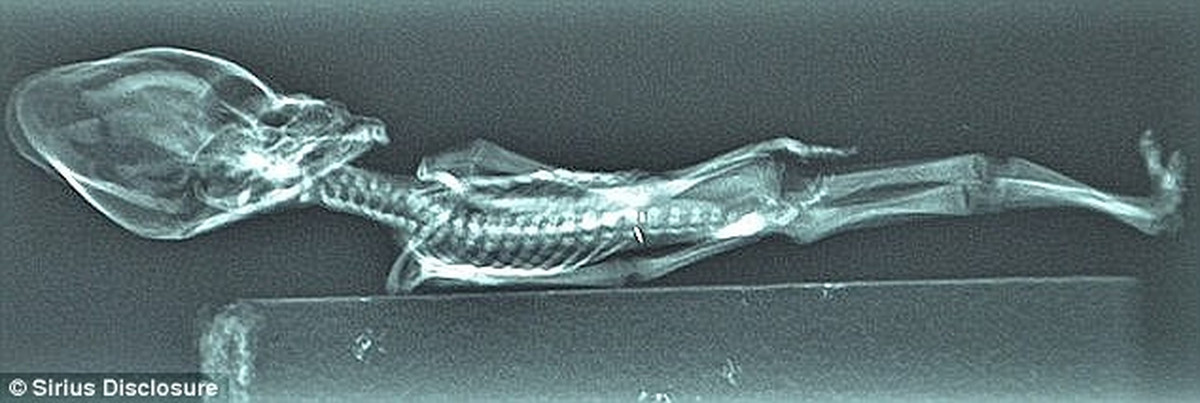

Năm 2003, Ata - xác ướp tí hon nghi của người ngoài hành tinh được phát hiện trong một chiếc bao nhỏ ở thị trấn khai thác mỏ La Noria bỏ hoang tại sa mạc Atacama của Chile.

Xác ướp Ata có hình dáng giống con người nhưng kích thước khá nhỏ, chỉ dài 15 cm, hộp sọ dài và hốc mắt lớn. Với hình dáng như vậy, một số người suy đoán đây không phải là hài cốt của con người mà có thể là xác của người ngoài hành tinh.

Cụ thể, các nhà nghiên cứu thuộc Đại học Stanford xác định xác ướp Ata là thi hài của con người sau khi phân tích bộ gene.

Ata là bé gái sơ sinh có nhiều đột biến gene gắn liền với chứng lùn, vẹo cột sống và nhiều bất thường ở hệ cơ và xương.

Garry Nolan, giáo sư vi sinh vật học và miễn dịch học ở Trường y thuộc Đại học Stanford, California, cho hay nhóm nghiên cứu xác định được 4 biến thể nucleotide đơn mới (SNV) - một dạng đột biến gene, ở những gene gây ra các bệnh về xương như chứng vẹo cột sống hoặc trật khớp cùng 2 SNV ở các gene liên quan đến sản sinh collagen.

Ata có 10 cặp xương sườn thay vì 11 như mọi người. Đây là đặc điểm chưa bao giờ gặp trước đó.

"Chúng tôi thực sự tin rằng, Ata là thai lưu hoặc chết ngay sau khi chào đời. Bé gái bị biến dạng nặng đến mức không thể bú sữa mẹ. Trong tình trạng đó, bé nên được đưa vào phòng chăm sóc đặc biệt dành cho trẻ sơ sinh", giáo sư Garry cho hay.

Tuy nhiên, do thời điểm đó các cơ sở y tế ở khu vực hẻo lánh của Chile chưa phát triển nên Ata không được điều trị kịp thời. Cô bé có lẽ là người Chile qua đời cách thời điểm phát hiện khoảng 40 năm.